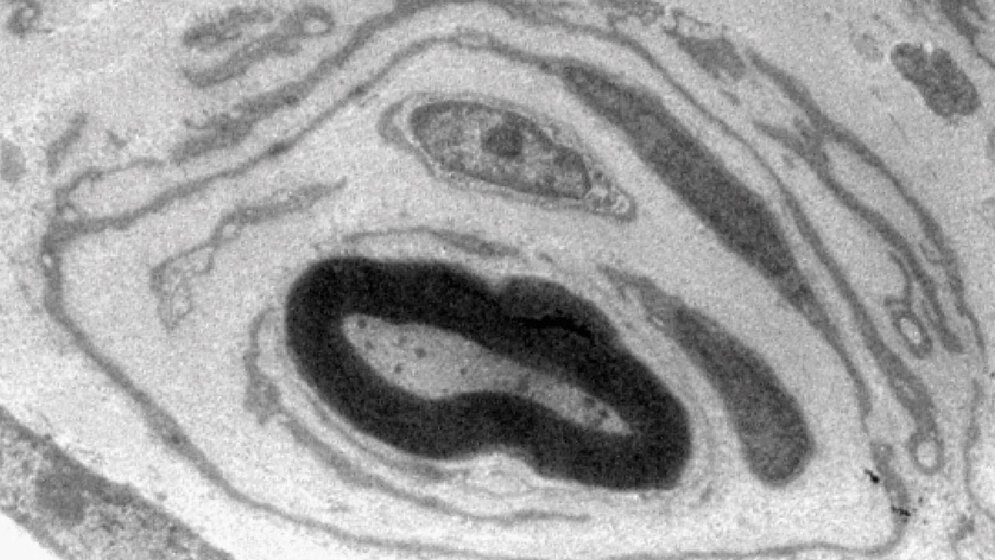

Unsere Nervenfasern sind wie Kabel elektrisch isoliert: Durch spezialisierte Zellen, den Schwann-Zellen, die sie mit einer fettreichen Scheide, dem Myelin, ummanteln. Dadurch können Signale besonders schnell weitergeleitet werden. Bei Menschen, die an der häufigsten vererblichen Neuropathie, der CMT1A-Erkrankung, leiden, ist die Interaktion zwischen Nervenfasern und Schwann-Zellen gestört. Nerven betroffener Patienten weisen im Querschnitt viele Fasern mit zahlreichen fehlerhaft angelagerten Schwann-Zellen auf. Dieses als „Zwiebelschalenformation“ bezeichnete Phänomen ist schon seit über 100 Jahren bekannt und dient Ärzten seither als wichtiges Diagnosekriterium. Ihre Entstehung ist aber komplett unverstanden.

Die Leipziger Forscher haben herausgefunden, dass Zwiebelschalenformationen Ausdruck eines aus dem Ruder gelaufenen Reparaturversuchs sind. „Das periphere Nervensystem hat die Fähigkeit, sich nach einer akuten Nervenschädigung, wie zum Beispiel einer Quetschung oder Schnittverletzung, selbst zu reparieren. Dabei ordnen sich die Schwann-Zellen hintereinander der Reihe nach an und bilden so ein langes Band, entlang dessen die Nervenfasern erneut auswachsen. Während dieser Zeit produzieren Schwann-Zellen den Wachstumsfaktor Neuregulin-1, ein zeitlich begrenztes Signal, das die Reparatur verletzter Nerven unterstützt“, erklärt Dr. Ruth Stassart von der Abteilung für Neuropathologie am Universitätsklinikum Leipzig, Seniorautorin der Studie. „In der CMT1A Erkrankung kommt es hingegen zu einer dauerhaften Produktion des Neuregulin-1 Signals in erkrankten Schwann-Zellen. Dies führt dazu, dass die Schwann-Zellen zahlreiche Reparaturbänder bilden, die jedoch in dieser Menge überhaupt nicht benötigt werden. So entstehen schlussendlich die zahlreichen Zwiebelschalenformationen, die wir in Nervenbiopsien von Patienten nachweisen können“, so die Wissenschaftlerin weiter.